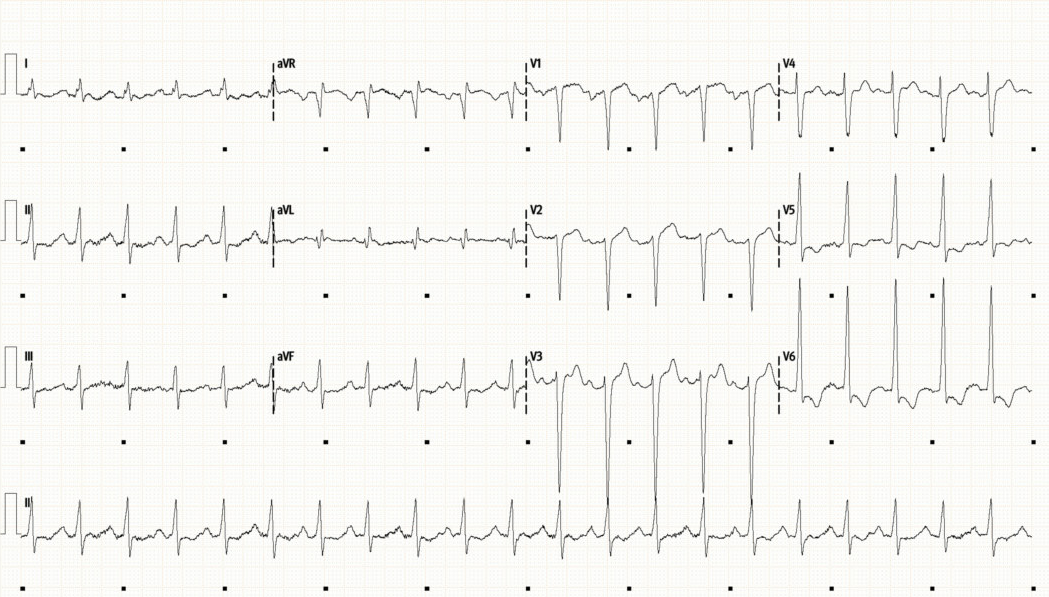

Initial ECG

• ECG:

• Sinus tachycardia with a rate of 130bpm.  QRS width at upper limit of normal (100ms).  LVH as signified by large-voltage QRS in precordial leads

• Marked ST depression and T-wave inversion in V5 and V6, ST elevation in aVR suggesting some subendocardial ischaemia

• An abnormal ECG, LVH and lateral changes raise the possibility of structural disease/cardiomyopathy whilst ST changes are also concerning for ischaemia (possible T1 MI or due to supply/demand mismatch)